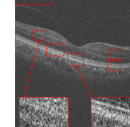

For testing the algorithm for the super-resolution of images of dataset3, 1 subject from each category has been selected and the algorithms have been applied for the super-resolution of artificially missed B-scans. Patch sizes were set equal to 5 and 7 with window size [2,2] and window size for MDT was set to [4,4] (recall that the window size for MDT has been selected for achieving the best output). The results have been presented in Fig. 7. Similar to the dataset2, in this dataset, no reference image is available and only visual comparison and CNR have been reported. CNR for each algorithm has been written beneath the resulting image. Visual comparison in addition to the resulting CNR’s, show the effectiveness of the proposed algorithm.

Original noisy image

Incomplete image

Spline interpolation

MDT [43]

Proposed algorithm